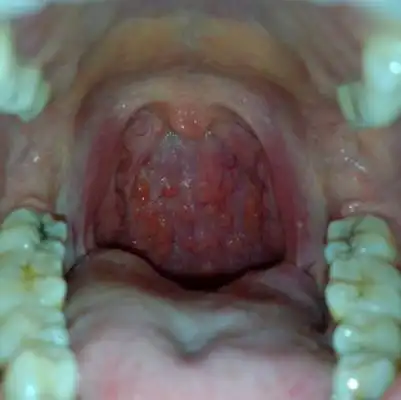

咽喉良性肿瘤

皮肤性病科图谱黏膜疾病口腔菜花样乳头瘤病

照片,喉部肿物分为良性肿物和恶性肿物,常见的良性肿物有喉乳头状瘤